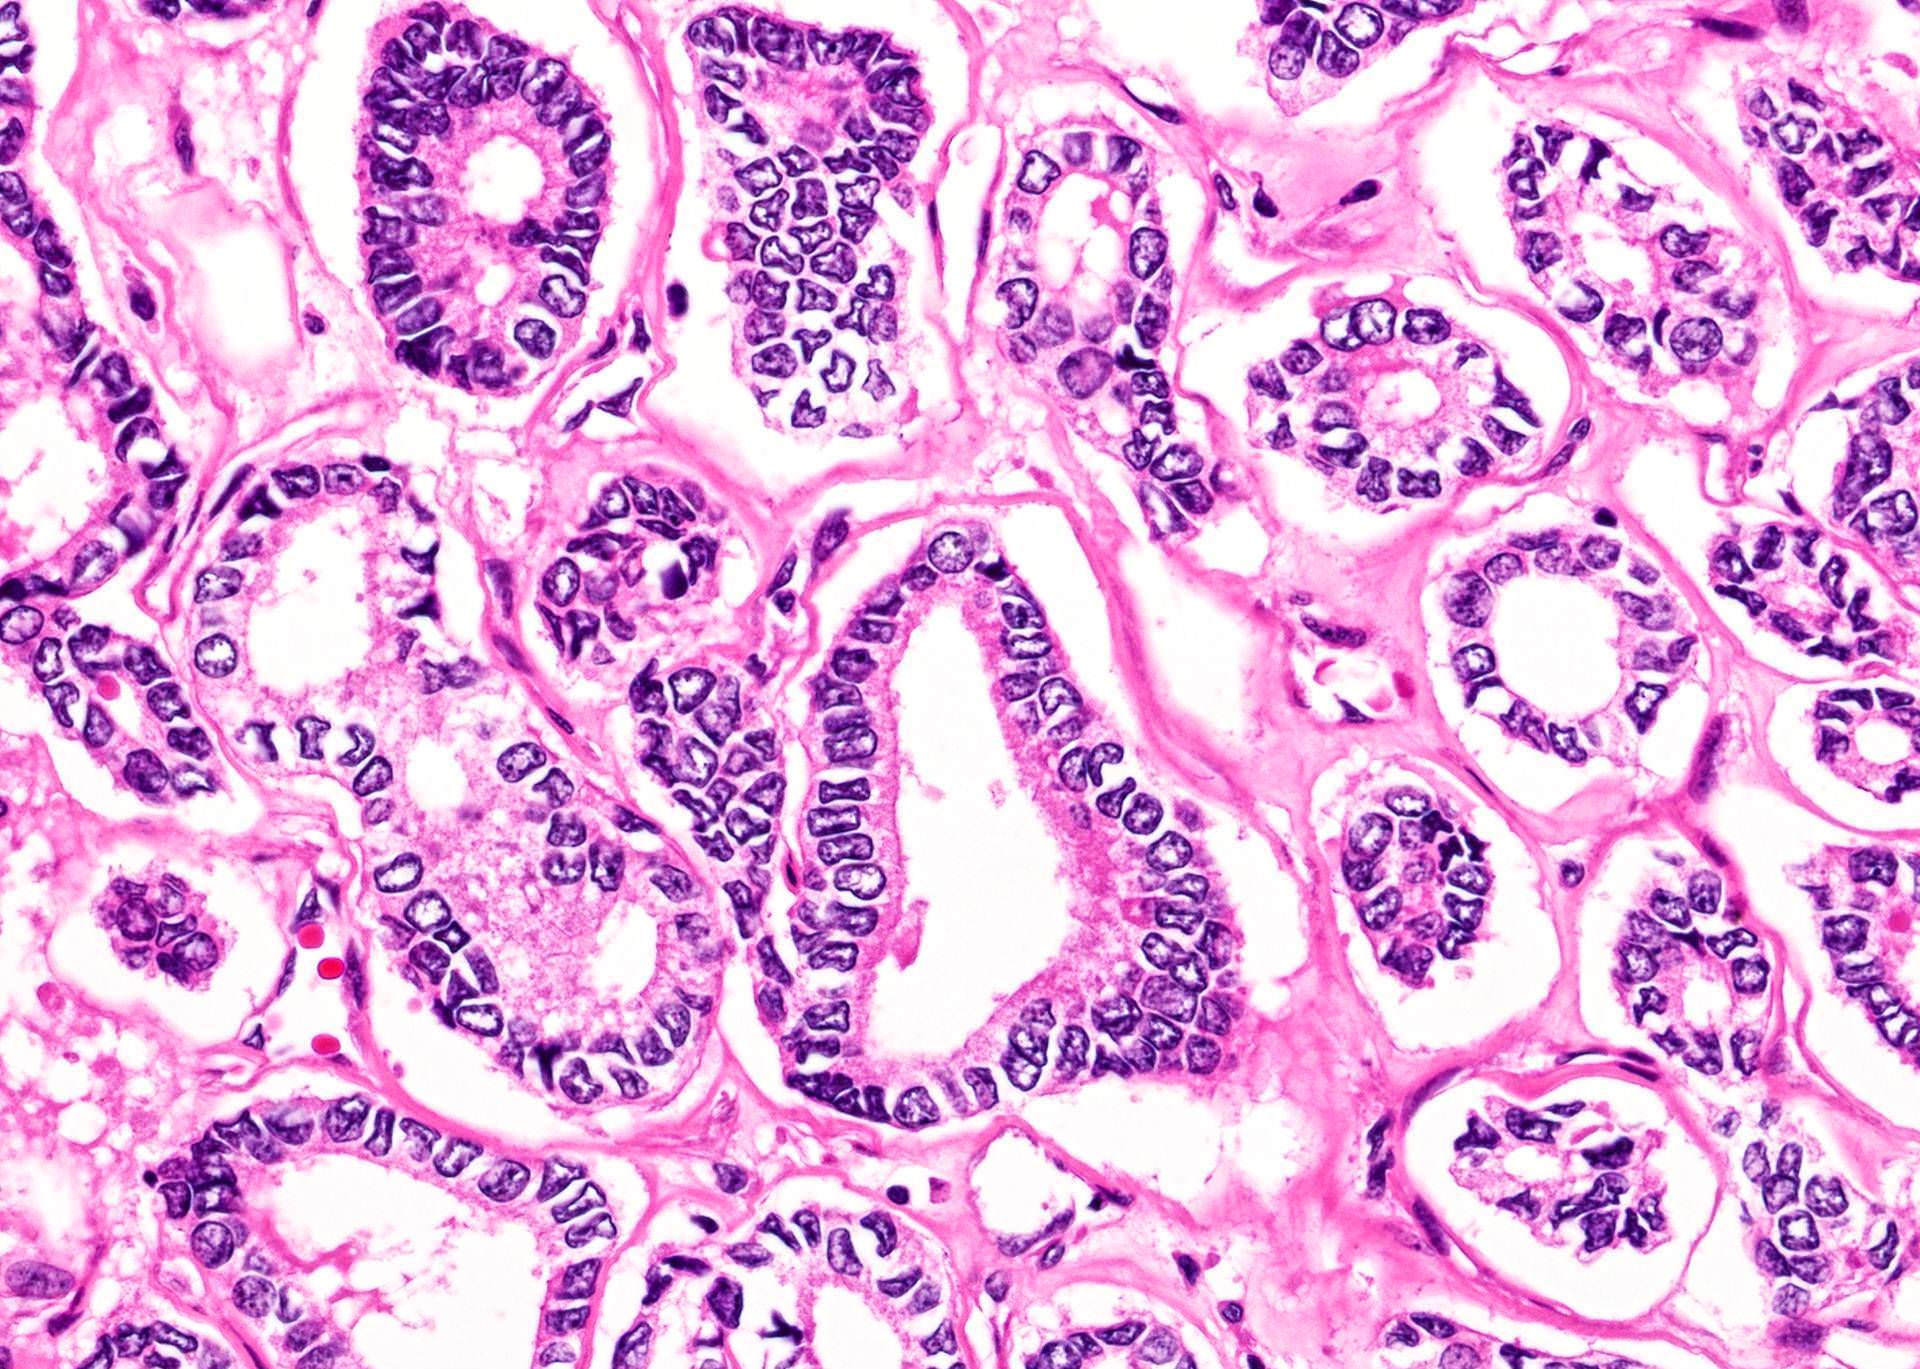

Microscopic (histologic) description

- Architecturally and cytologically different from surrounding gland

- Compression signs in surrounding thyroid tissue

- Encapsulated; thin or moderately thick capsule

- Architectural patterns (can be seen in any combination)

- Microfollicular (fetal): smaller follicles, small amount of intraluminal colloid

- Solid / trabecular (embryonal): minimal or no colloid

- Cuboidal to low columnar cells

- Small round nuclei, smooth nuclear boundary, uniformly hyperchromatic or euchromatic, dense chromatin, absent nuclear features of papillary thyroid carcinoma, nuclear score 0 or 1 (JAMA Oncol 2016;2:1023)

- Inconspicuous nucleoli

- Mitoses are uncommon

- Scant stroma

- Hyperfunctioning adenoma (Plummer adenoma): tall columnar epithelium, papillary infoldings, vacuolated cytoplasm, watery colloid showing scalloping

- Follicular adenoma with papillary hyperplasia: cystically dilated follicles, intraluminal papillae

Microscopic (histologic) images

Contributed by Shipra Agarwal, M.D., Andrey Bychkov, M.D., Ph.D., Mark R. Wick, M.D., Asmaa Gaber Abdou, M.D. and AFIP

Patterns: